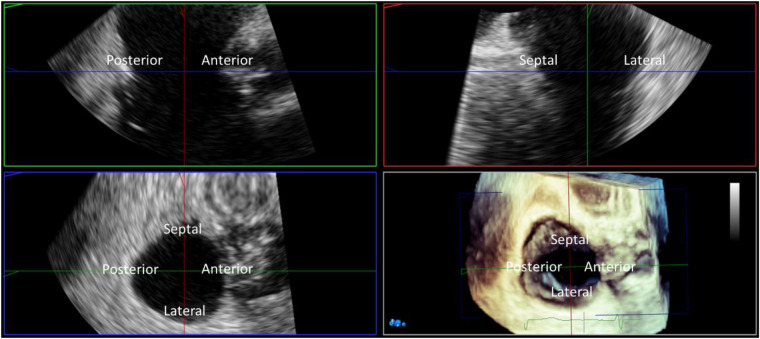

Figure 6.

Three-dimensional (3D) TEE multiplanar reconstruction. 3D imaging with multiplanar reconstruction of the tricuspid valve from the mid esophageal window in mid diastole. The 3D block is presented in the ‘non rotated’ view with the reconstructed long axis 2D images displayed in the familiar ‘commissural’ and corresponding septo-lateral orthogonal image. Direct measurement of tricuspid annular dimensions is performed from planimetry of the 2D short axis image aligned with the tricuspid annulus.